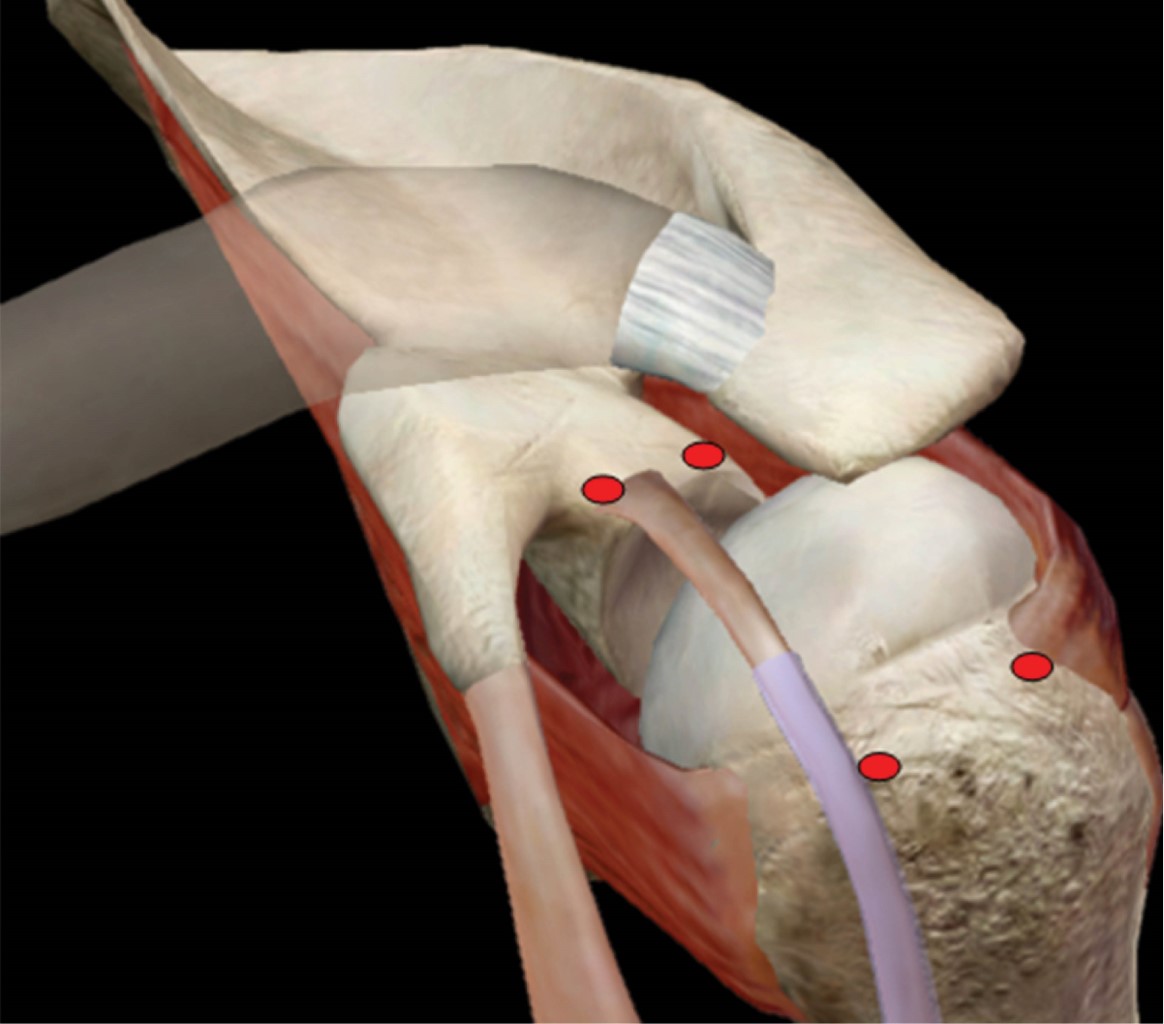

From www.arthroscopytechniques.org

Arthroscopic Superior Capsular Reconstruction for Massive Irreparable Rotator Cuff Repair Rotator Cuff Capsular Pattern according to dutton, capsular patterns are based on clinical findings rather than research; stage 1, the preadhesive stage, demonstrates mild erythematous synovitis. frozen shoulder can develop after a shoulder has been immobilized (held in one position without moving) for a period of time due to surgery, a fracture, or. adhesive capsulitis (also known as frozen shoulder). Rotator Cuff Capsular Pattern.

Arthroscopic Superior Capsular Reconstruction for Massive Irreparable Rotator Cuff Repair Rotator Cuff Capsular Pattern examples include a rotator cuff tear and fractures of your shoulder blade, collarbone or upper arm. stage 1, the preadhesive stage, demonstrates mild erythematous synovitis. The primary way to distinguish rc pathologies from frozen shoulder is to examine the specific. rotator cuff (rc) pathologies. frozen shoulder can develop after a shoulder has been immobilized (held in. Rotator Cuff Capsular Pattern.

From onlinelibrary.wiley.com

Advancement in Arthroscopic Superior Capsular Reconstruction for Irreparable Massive Rotator Rotator Cuff Capsular Pattern stage 1, the preadhesive stage, demonstrates mild erythematous synovitis. frozen shoulder can develop after a shoulder has been immobilized (held in one position without moving) for a period of time due to surgery, a fracture, or. rotator cuff (rc) pathologies. Perhaps that's why the capsular patterns may be different. examples include a rotator cuff tear and. Rotator Cuff Capsular Pattern.